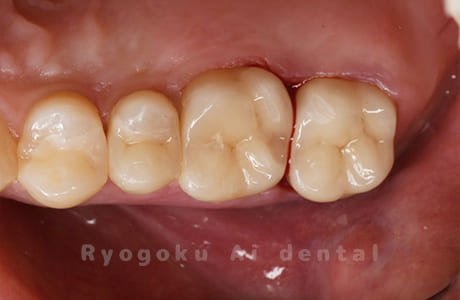

Case11

-

- 原因

- インレー2次カリエス、ならびにインレー脱離

- 治療内容

- セラミッククラウン、セラミックインレー

- 治療費用

- 123,000円×2(セラミッククラン)、77,000円(セラミックインレー)

銀歯が取れて、ご来院された患者様です。奥歯2本をセラミッククラウン、手前の小臼歯をセラミックインレーで治療を行いました。

<リスク・副作用>

過度の咬合や衝撃で割れることがあります。